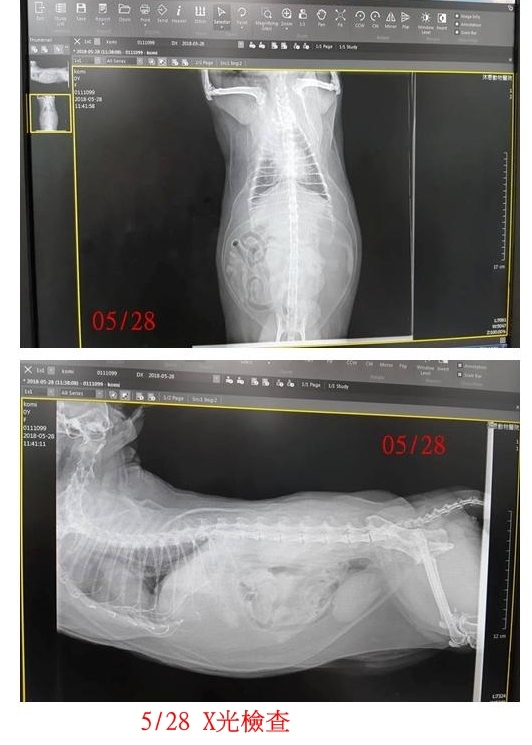

[5/28]

Call me沐恩回診 林文傑醫師

體重:7.2體重上升上回是7.09

《回診狀況》

這次血檢進步很多,上次疑似有出血問題,是因為服用類固醇產生的副作用,但這次血檢都有回升,都有變好,AST也都正常,球蛋白GLOB已由6.7降回5.9(變好),可能因為停了一週類固醇,水分攝取不太夠,腎指數高一些。

喉嚨聲音變大,膿太多往後流至喉嚨與鼻腔的地方,就會發出咕咕咕的聲音,所以類固醇須再回復使用(以往的一半劑量)

今日有拍X光,X光看肺部還好,沒有那麼糟,目前內視鏡已修好,可邊看邊清理膿塊,沖洗較徹底。

接著看一週吃藥效果,如未改善就得安排內視鏡清理,下週回診。